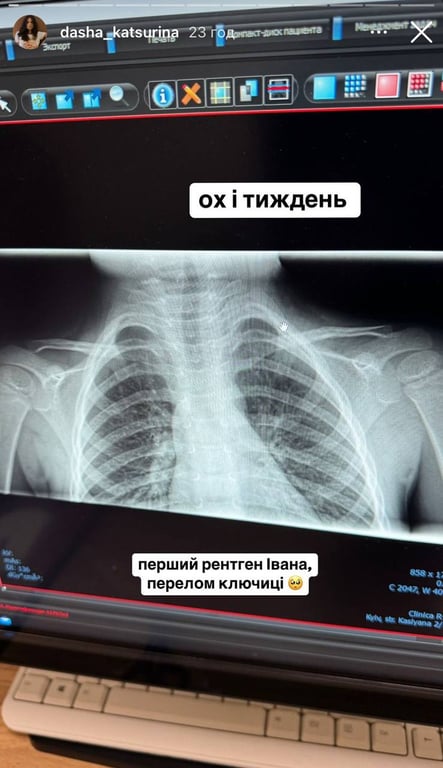

Даша Кацуріна розповіла, що  днями Івану потрібно було терміново робити перший в житті рентген. Згодом Даша розсекретила причину звернення до лікарів.

"Ох і тиждень. Перший рентген Івана, перелом ключиці. Перенервувала я сильно", — написала дизайнерка.

Рентген сина Даші Кацуріної

Рентген сина Даші Кацуріної. Фото: instagram.com/dasha_katsurina/

"Дитячі переломи ключиці рятують бандажами, жодних гіпсів. Ще плюс — це ставлення Івана до життєвих негараздів, пощастило нам", — додала Кацуріна.